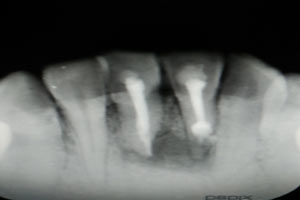

圖2.術(shù)前的根尖片影像、31根管治療已做,欠填少許。31、41根尖有橢圓形陰影,未見(jiàn)明顯骨白線。

圖3.術(shù)中x線片檢查:31預(yù)備植根中1/3與根尖1/3遇阻力,根管測(cè)量無(wú)法測(cè)到長(zhǎng)度,根尖1/3牙膠無(wú)法取出。

圖6.根管治療+樹(shù)脂充填后根尖片影像:31根尖1/3大量根充物溢出。因此必須同期根管外科治療

圖18.術(shù)后的根尖片影像檢查: